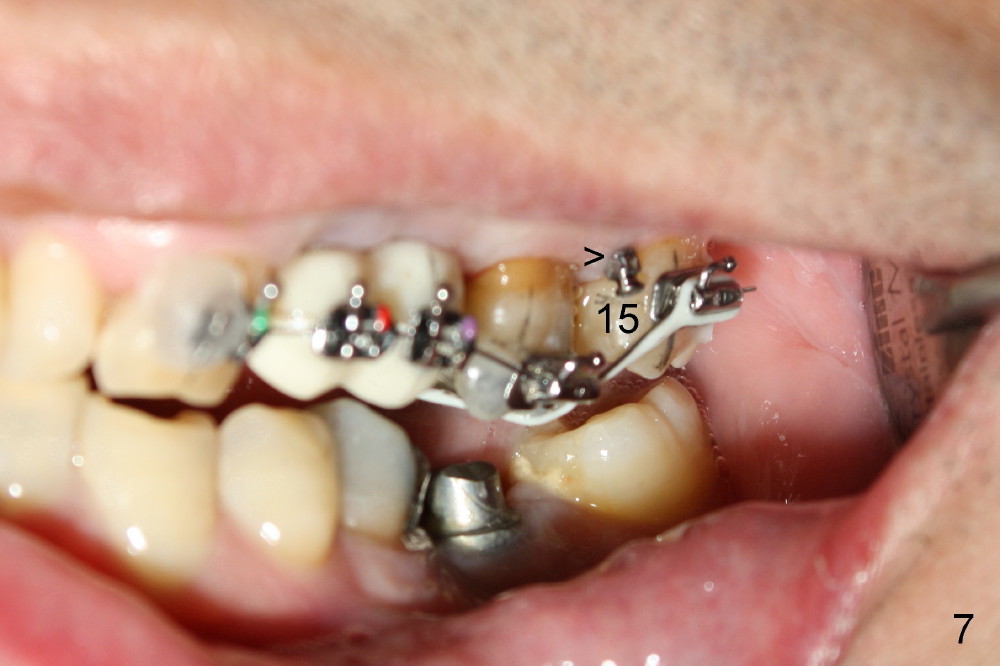

A 51-year-old man needs implants at the sites of #12,13,19 (Fig.1). The teeth #12 and 13 are extracted. An implant is placed at #19 (Fig.2 <). After osteointegration, an abutment is placed (Fig.2 A). The opposing tooth, #14, is found supraerupted. Two mini-implants are placed at the mesiobuccal and distolingual areas of #14 (Fig.3 (mirror view) <) and a power chain (*) is placed for intrusion. In the next 8 months, these 2 mini-implants become loose. Two new mini-implants are placed in the mesiolingual and distobuccal regions (Fig.4 ^). The one in the distobuccal region is loose after a while (Fig.6,7 >). In brief, mini-implants are not efficient in intrusion. At this time, the implants at the sites of #12,13 apparently osteointegrate (3 months post placement) and abutments are placed (Fig.4). Provisional crowns are fabricated (Fig.5). Brackets are placed between #11 and 15 with the bracket at #14 placed more coronally than those of the neighboring teeth (Fig.6-8). Mesially there are two excellent anchorages (#12,13) as well as the mesiolingual mini-implant. The distal anchorage is #15. In the next 5.5 months, the tooth #14 is intruded (Fig.9,10), but the 2nd molar is mobile (not as strong as #14). A longer mini-implant is placed in the distobuccal corner (>, more apical than before (Fig.7)). The distobuccal mini-implant is found to be mobile in 3 weeks (Fig.11). It appears that there is enough clearance for restoration of #19 (Fig.12). Power chains are placed between the mesiolingual mini-implant and #14 buccal tube until the appointment for crown prep. In this way, the lingual cusps may ascend (Fig.13 red arrow), while the buccal ones may descend (black arrow). The occlusal clearance will be more favorable.